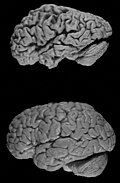

Gross

Features:

- Temporal atrophy, esp. hippocampus.

- Dilation of:

- Lateral ventricles.

- Third ventricle.

- Frontal and temporal lobe atrophy.